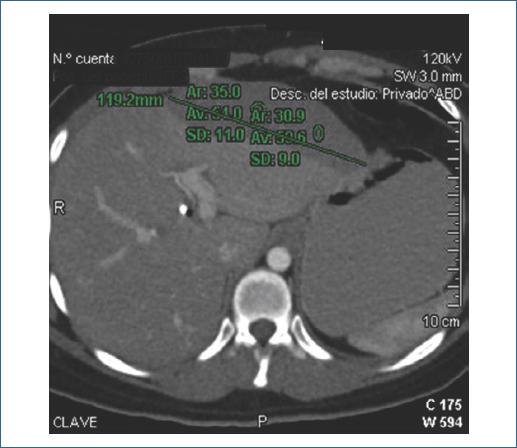

Paciente de sexo femenino de 29 años, sin antecedentes de importancia. Ingresa por cuadro de cólico biliar e ictericia. El ultrasonido evidenció coledocolitiasis, por lo que se realizó CPRE. Durante el procedimiento, con un tiempo de canulación de 5 minutos, se efectuaron dos intentos de canulación con guía hidrofílica por parte del médico adscrito en turno, asistido por el residente de endoscopia. Se realizó esfinterotomía, identificando cístico de implantación media sin defectos de llenado; se efectuaron barridos con balón, obteniéndose salida de lodo biliar, y se colocó una endoprótesis biliar. Se concluyó que se trataba de un síndrome de Mirizzi tipo I. Durante la noche, la paciente presentó dolor abdominal súbito. Los laboratorios relevantes posteriores al procedimiento fueron: bilirrubina total (BT) 6.46, directa (BD) 1.25, indirecta (BI) 5.21; aspartato aminotransferasa (AST) 53, alanina aminotransferasa (ALT) 212, fosfatasa alcalina (FA) 189, gamma-glutamil transferasa (GGT) 429, lactato deshidrogenasa (DHL) 202, amilasa 111, lipasa 261. Se realizó tomografía computarizada (TC), que evidenció una colección subcapsular en el lóbulo hepático izquierdo de 172 ml (Fig. 1). Se manejó de forma conservadora, con 12 días de estancia intrahospitalaria y adecuada evolución, por lo que se indicó egreso por mejoría clínica, con programación para colecistectomía laparoscópica.